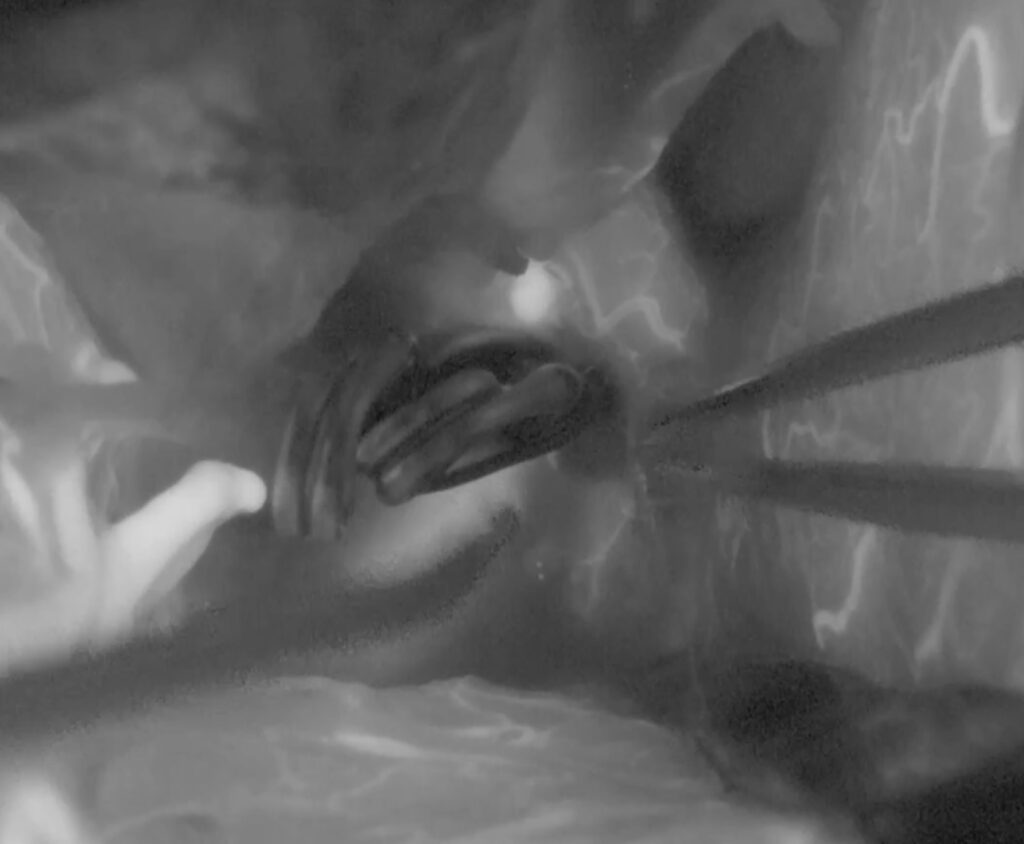

最近のこの場所の動脈瘤クリッピング術が増えています。4mm以上の上向き動脈瘤で術前BTOで虚血耐性のあるものを適応としています。ICG、MEP、VEG、術中血管撮影など術中画像、電気生理学モニタリングをしっかり準備して行っています。本例も視神経下面と癒着しており、剥がすときに破れましたが、問題なくクリップできています。術後の視機能も良好でした。

術後嗄声と2/23より髄液鼻漏れがあり、CTで左篩骨洞に髄液貯留があり5日間の腰椎ドレナージを行い、治癒しました。